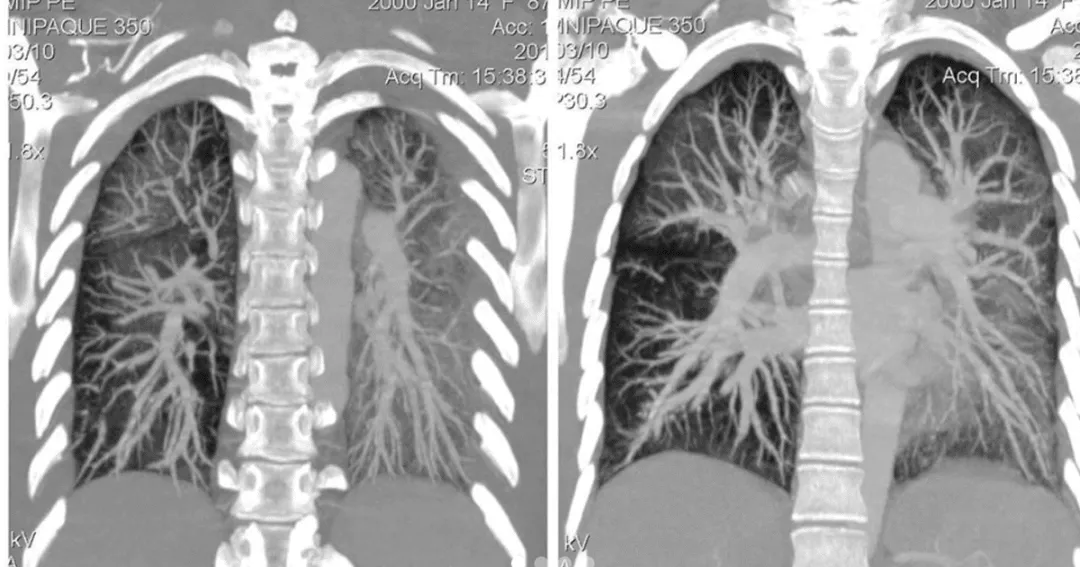

4. 重症患者6个月后肺功能还没有完全恢复。在发病6个月后,住院时病情更重的患者更可能呈现肺功能下降和胸部影像学异常。

5. 新冠除了肺部,还会攻击其他器官。我们知道新冠病毒进入人体后主要攻击肺部,但越来越多的研究证据表明,除了肺部,身体的其他部位也受到伤害。

其实,新型冠状病毒肺炎的患者胸部CT或胸片不都是“白肺”,在患病初期,双肺的CT显示正常,但随着疾病发展,若没有得到治疗,肺部便会出现病变加重,也就是俗称“磨玻璃”影。